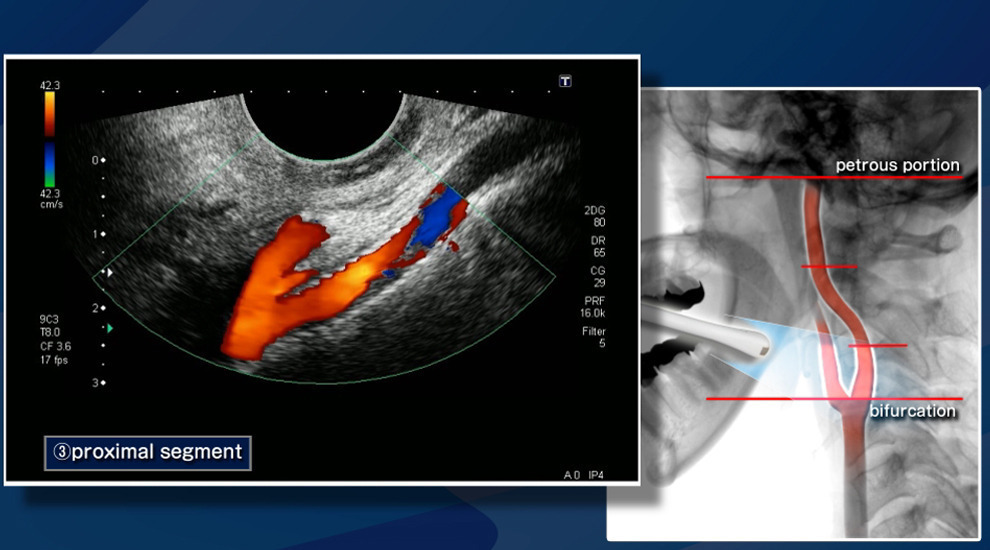

경동맥 초음파 검사는 목 양쪽에 위치한 경동맥의 혈류 상태와 혈관 벽의 두께, 그리고 동맥경화 정도를 확인하기 위해 시행되는 비침습적 영상 검사입니다. 경동맥은 뇌로 혈액을 공급하는 주요 혈관으로, 이곳에 이상이 생기면 뇌졸중, 일과성 허혈 발작 등 중대한 질환으로 이어질 수 있습니다. 특히 증상이 나타나기 전 조기 진단이 가능하다는 점에서 예방적 의미가 매우 큽니다.

경동맥 초음파는 단순히 혈관이 막혔는지를 확인하는 데 그치지 않고, 혈관 벽의 두께 변화나 혈류 패턴을 분석해 다양한 질환을 조기에 발견할 수 있습니다.

결과지에는 혈류 속도, 혈류 방향, 플라크의 형태 및 위치 등이 함께 기재됩니다. 영상 분석을 통해 플라크의 안정성 여부를 평가하면 향후 뇌졸중 위험 예측에도 도움이 됩니다.